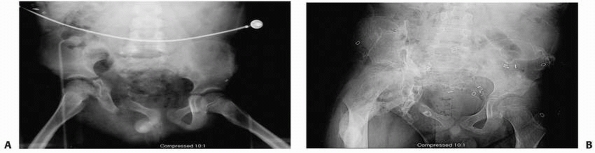

![]() |

FIGURE 20-19 This radiographic series highlights treatment of the unstable pelvic fracture with hemodynamic instability. A.

Anteroposterior pelvis radiograph of a 12-year-old male who was a pedestrian hit by a car. There is a wide symphysis and a displaced fracture adjacent to the left sacroiliac joint. The towel clips seen on radiograph are to hold a sheet (sling) around the pelvis to help temporarily control hemorrhage. B. CT scan showing the displaced posterior injury. C. Pelvis radiograph after an anterior external fixation was placed urgently to stabilize the pelvis. This along with resuscitation stabilized the hemodynamic status. D. Once the patient had stabilized, the external fixation was converted to anterior internal fixation with a plate on the symphysis pubis and the posterior instability was treated with a sacroiliac screw. |